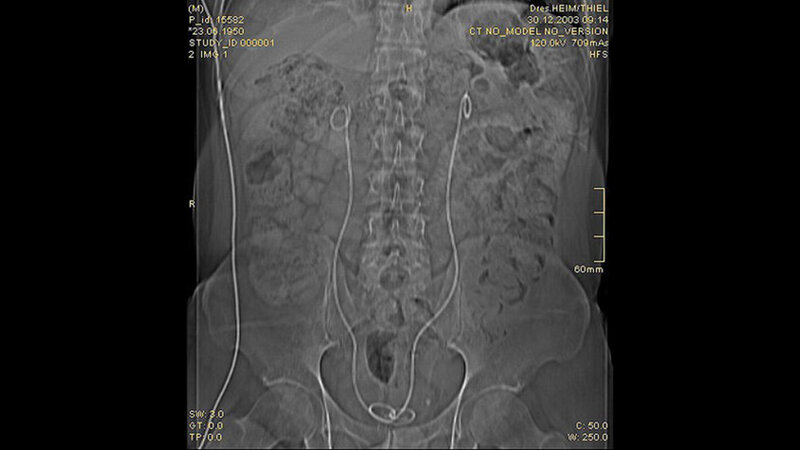

Der Morbus Ormond ist eine seltene Erkrankung, durch eine entzündliche Fibrose des Retroperitoneums charakterisiert. Die klinische Symptomatik ist unspezifi sch und kann abdominelle, Rücken- oder Flankenschmerzen beinhalten. Eine Komplikation kann durch Alteration der Harnleiter mit obstruktiver Nephropathie entstehen. Therapeutische Maßnahmen sind Glucocorticoide, Implantation einer Doppel-J-Schiene und die chirurgische Behandlung.